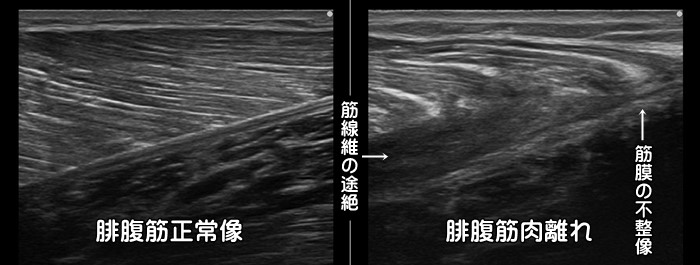

ふくらはぎ・腓腹筋の肉離れ

急なダッシュ動作やスピード練習で発症します。中高年に好発します。多くはふくらはぎの腓腹筋の内側に発症します。筋線維が途中で断裂するのではなく、筋肉を包む筋膜から剥がれるように損傷します。剥離した部分には血腫が見られます。通常肉眼での皮下出血は受傷から2~3日後に確認できます。